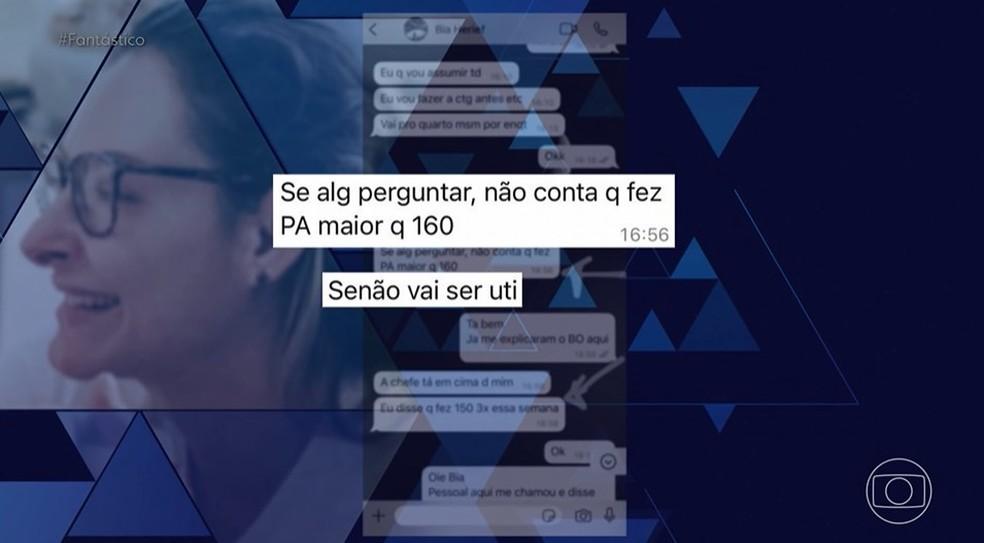

Outro relato impactante foi o de Bianca Angelim, que afirmou que seu filho “nasceu morto” após complicações durante um parto supostamente induzido de forma inadequada. “Custou a vida do meu filho”, disse Bianca, explicando como foi orientada a mentir sobre sua condição de saúde para não ser encaminhada à UTI.